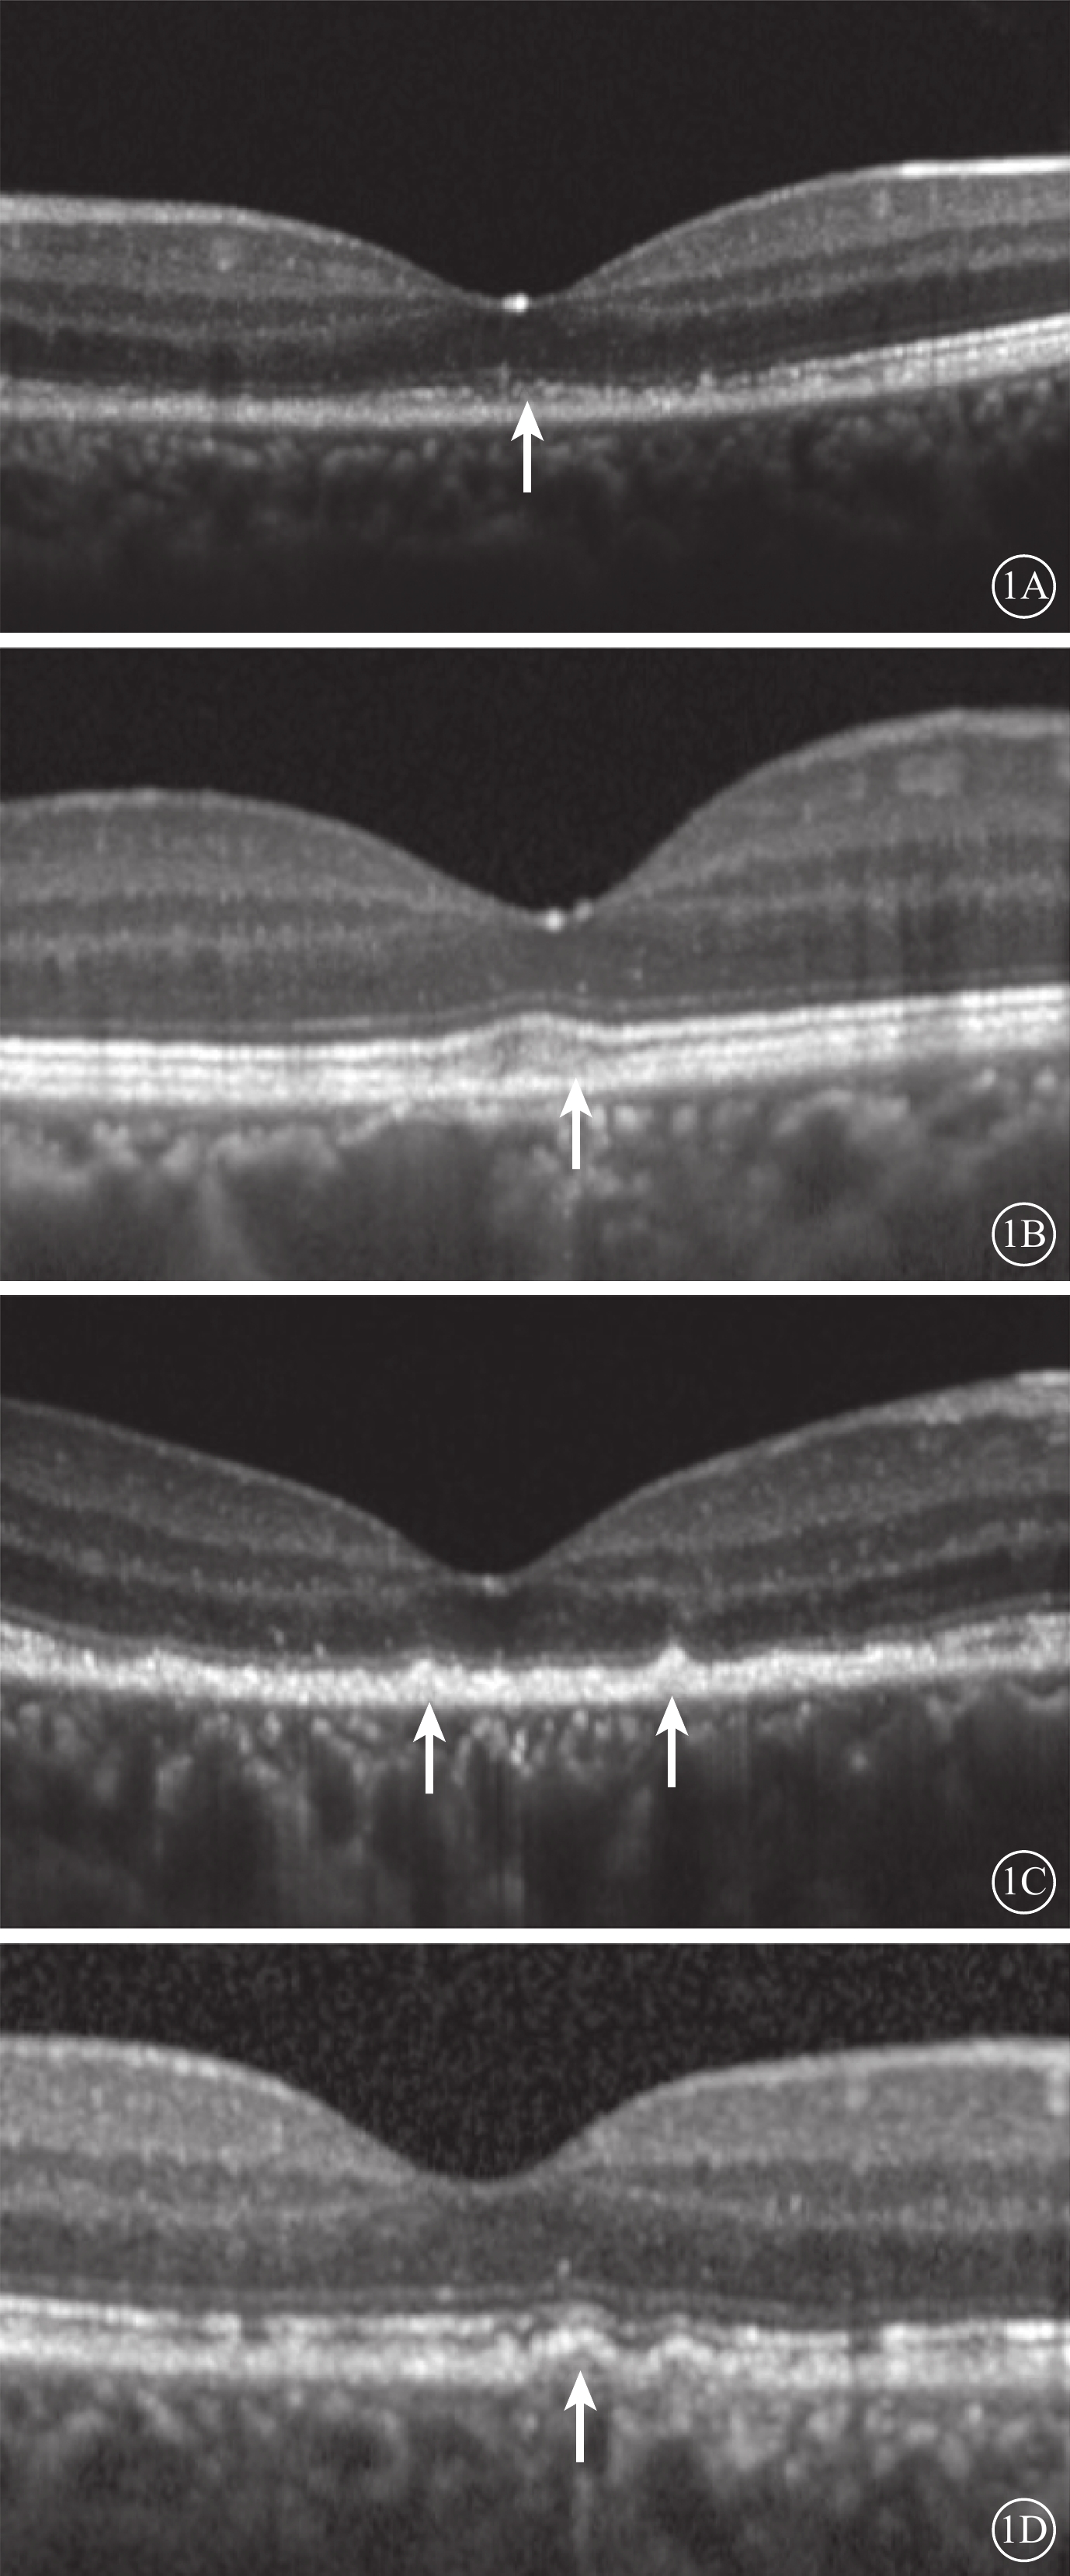

采用法國光太Supra Scan 577 nm多點掃描距陣激光器的持續激光模式或微脈沖激光模式。CLT治療參數:曝光時間0.05 s,光斑直徑100 μm,能量50~60 mW,光斑數量18~27個。SLT治療采用Supra Scan 577 nm微脈沖激光模式。治療參數:曝光時間2.00 ms,占空比5%,光斑直徑160 μm,能量250~400 mW。兩種治療方式的治療區域均為滲漏點周圍區域。所有治療均由同一位經驗豐富的眼底病醫生完成。由一位有經驗的特檢科醫生采用SD-OCT儀(Heidelberg Eye Version 1.8.6.0頻域OCT系統),對中心凹進行9 mm橫、豎單線掃描,以及黃斑區6 mm×6 mm范圍內25個斷面橫掃描,并采用隨訪模式保證每次隨訪掃描時的位置不變。選取經過中心凹的水平方向掃描圖像用于視網膜微結構評估。定性評估包括中心凹下EZ、嵌合體帶(IZ)的完整性和RPE平滑性。EZ、IZ完整性分為完整或不完整,不完整定義為OCT下相應層次連續性中斷(圖1A,1B)。RPE平滑性分為平滑或粗糙,粗糙定義為RPE局部隆起(圖1C)、RPE脫離(PED)(圖1D)、RPE增厚。定量評估包括中心凹視網膜厚度(CFT)和外核層(ONL)、內節(IS)、OS厚度。CFT定義為內界膜(ILM)內界至RPE外界的垂直距離。ONL定義為ILM外界至外界膜(ELM)內界的垂直距離。IS定義為ELM至EZ外界的垂直距離。OS定義EZ外界至RPE內界的垂直距離(圖2)。上述所有評價指標均由兩位眼科醫生分別盲態下單獨讀取,其中定量指標取兩者平均值納入統計,定性指標若存在爭議進一步討論并確定最終結果。

圖1

視網膜微結構定性評價示意圖。1A示EZ完整性破壞(白箭);1B示IZ完整性破壞(白箭);1C示RPE局部隆起(白箭);1D示PED(白箭)

圖1

視網膜微結構定性評價示意圖。1A示EZ完整性破壞(白箭);1B示IZ完整性破壞(白箭);1C示RPE局部隆起(白箭);1D示PED(白箭)

采用法國光太Supra Scan 577 nm多點掃描距陣激光器的持續激光模式或微脈沖激光模式。CLT治療參數:曝光時間0.05 s,光斑直徑100 μm,能量50~60 mW,光斑數量18~27個。SLT治療采用Supra Scan 577 nm微脈沖激光模式。治療參數:曝光時間2.00 ms,占空比5%,光斑直徑160 μm,能量250~400 mW。兩種治療方式的治療區域均為滲漏點周圍區域。所有治療均由同一位經驗豐富的眼底病醫生完成。由一位有經驗的特檢科醫生采用SD-OCT儀(Heidelberg Eye Version 1.8.6.0頻域OCT系統),對中心凹進行9 mm橫、豎單線掃描,以及黃斑區6 mm×6 mm范圍內25個斷面橫掃描,并采用隨訪模式保證每次隨訪掃描時的位置不變。選取經過中心凹的水平方向掃描圖像用于視網膜微結構評估。定性評估包括中心凹下EZ、嵌合體帶(IZ)的完整性和RPE平滑性。EZ、IZ完整性分為完整或不完整,不完整定義為OCT下相應層次連續性中斷(圖1A,1B)。RPE平滑性分為平滑或粗糙,粗糙定義為RPE局部隆起(圖1C)、RPE脫離(PED)(圖1D)、RPE增厚。定量評估包括中心凹視網膜厚度(CFT)和外核層(ONL)、內節(IS)、OS厚度。CFT定義為內界膜(ILM)內界至RPE外界的垂直距離。ONL定義為ILM外界至外界膜(ELM)內界的垂直距離。IS定義為ELM至EZ外界的垂直距離。OS定義EZ外界至RPE內界的垂直距離(圖2)。上述所有評價指標均由兩位眼科醫生分別盲態下單獨讀取,其中定量指標取兩者平均值納入統計,定性指標若存在爭議進一步討論并確定最終結果。

圖1

視網膜微結構定性評價示意圖。1A示EZ完整性破壞(白箭);1B示IZ完整性破壞(白箭);1C示RPE局部隆起(白箭);1D示PED(白箭)

圖1

視網膜微結構定性評價示意圖。1A示EZ完整性破壞(白箭);1B示IZ完整性破壞(白箭);1C示RPE局部隆起(白箭);1D示PED(白箭)